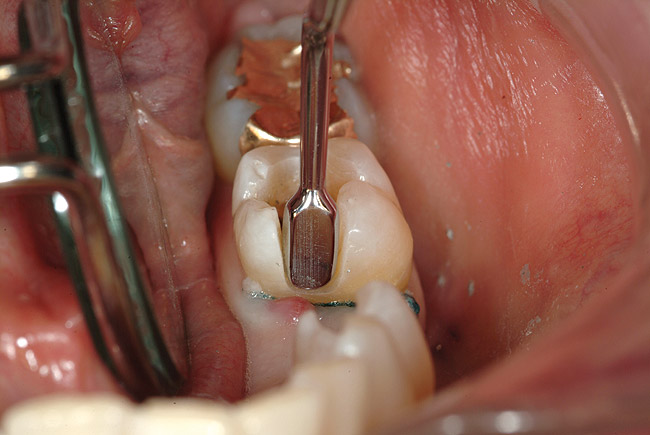

Figure 6b  Sizing instrument to prepare the proximal box to an adequate width for the Tescera quartz fiber U-Beam.

Figure 6b

Figure 6c  Inlay preparations of abutment teeth for a FPD.

Figure 6c

Figure 6d  From this facial view, the opaque U-Beam is apparent in the gingival aspect of the proximal portion of the restoration.

Figure 6d